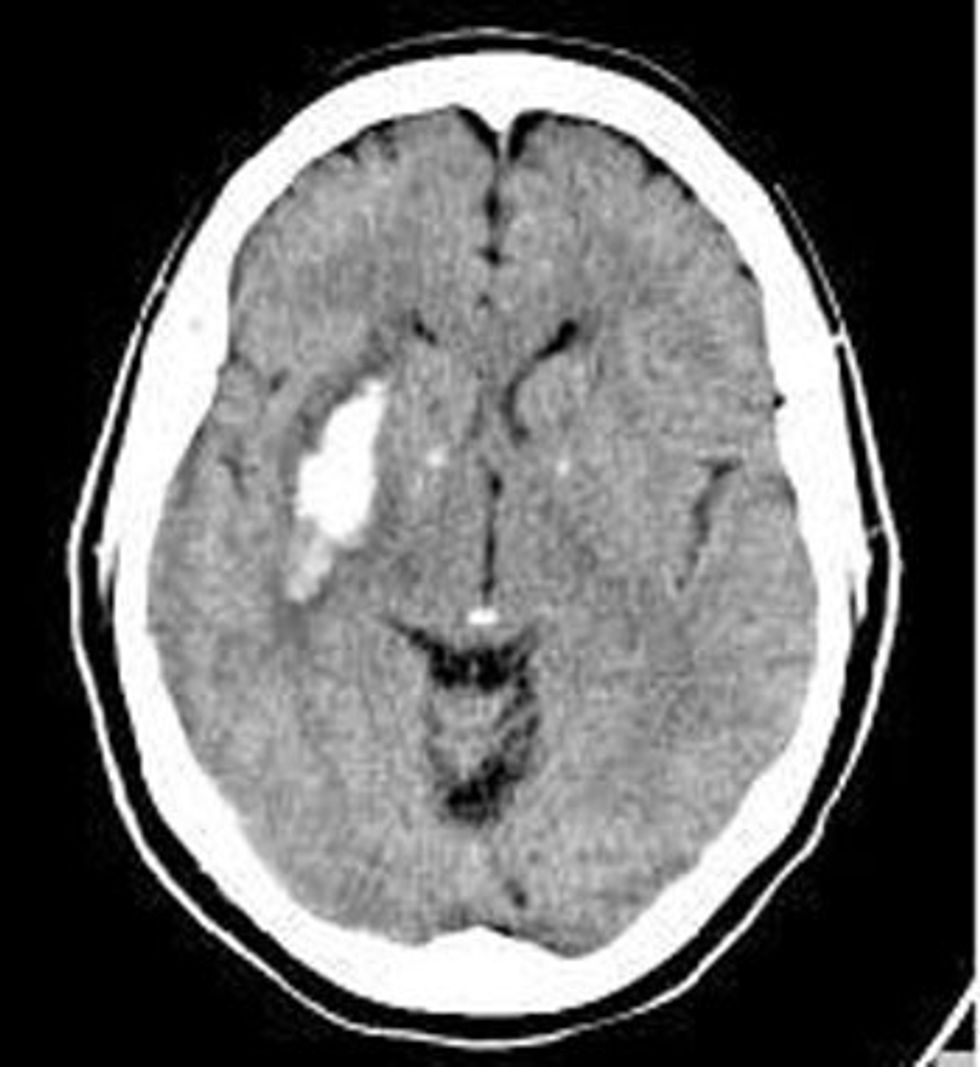

CT endocraniumi ku shihet hematoma intracerebrale në regjionin e ganglioneve bazale djathtas